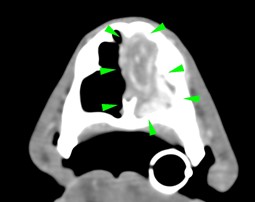

An 11-year-old cocker spaniel was referred to Eastcott Referrals for a chronic nasal discharge and soft tissue swelling in the dorsal aspect of the nose. A CT scan of the head showed a complete obstruction of the left nasal cavity, due to the presence of an amorphous soft tissue mass, extending through the left nasal meatus, left nasal conchae, left sided endoturbinates, left sphenoidal sinus and left frontal sinus (green arrowheads). Bilateral disruption of the turbinates was visible (yellow arrowheads), along with lysis of the left frontomaxillary suture, palatine suture, left rostral portion of the cranium (purple arrowheads) and nasal septum, which was also displaced to the right side